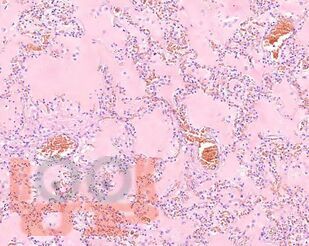

В учебном пособии представлен теоретический материал, перечень макропрепаратов и микропрепаратов, демонстрирующих типовые проявления патологических процессов и нозологических форм заболеваний. В цветных иллюстрациях и в описании микропрепаратов сделан акцент на наиболее важных гистологических изменениях, позволяющих на светооптическом уровне диагностировать и дифференцировать состояния, отклоняющиеся от нормы, в том числе с использованием различных гистологических окрасок. Пособие помогает выделить главные аспекты изучаемых патологических процессов, организовать и конкретизировать учебный процесс.